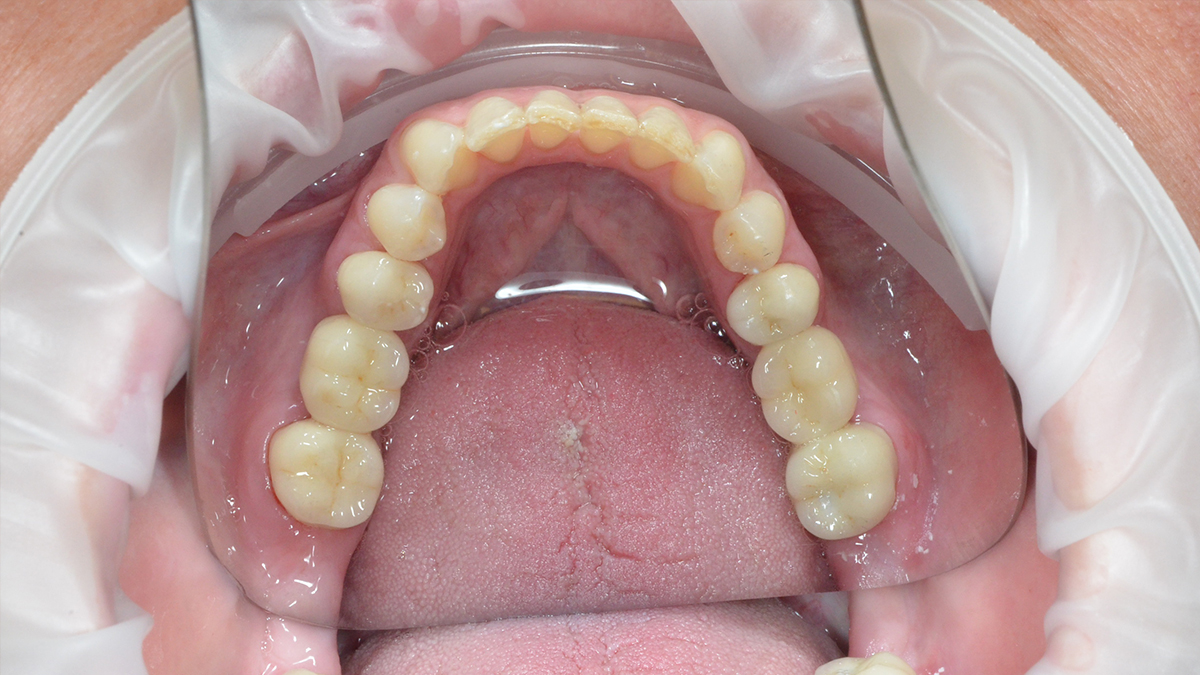

Általában ha a fognak csak egy kisebb része szuvas, a hiányzó rész kitisztítás után tömőanyaggal pótolható. A töméskészítést helyi érzéstelenítésben végezzük, egy alkalmat vesz igénybe. A tömőanyag egy speciális műanyag, kompozit, amely mind színében, mind fizikai tulajdonságaiban nagymértékben hasonlít a természetes foghoz, ezért alkalmas tartós és esztétikus tömések készítésére. Töméskészítés során a gyurmaszerű anyagot kis adagokban helyezzük az üregbe, majd az egyes rétegeket speciális lámpával világítjuk meg, melynek hatására megszilárdulnak. A tömés elkészültével az anyag kötése befejeződik, a fog terhelhető.

A tömőanyag tulajdonságaiból adódóan ma már, ha az üreg nem túl nagy, minden fogcsoport tömésére alkalmazható. Rágófogakban képes helyreállítani a funkciót, azaz egy erős, a rágóerőkkel szemben ellenálló tömés készíthető, frontfogakba (metszőfogak) pedig készülhet olyan esztétikus, észrevehetetlen tömés, mely kedvezően befolyásolhatja megjelenésünket, arckarakterünket.